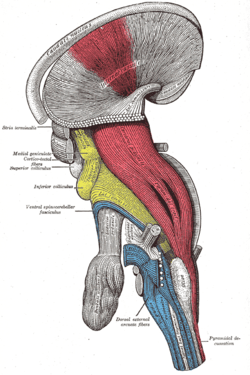

Deep dissection of brain-stem. Lateral view.

Deep dissection of brain-stem. Lateral view. Superficial dissection of brain-stem. Ventral view.